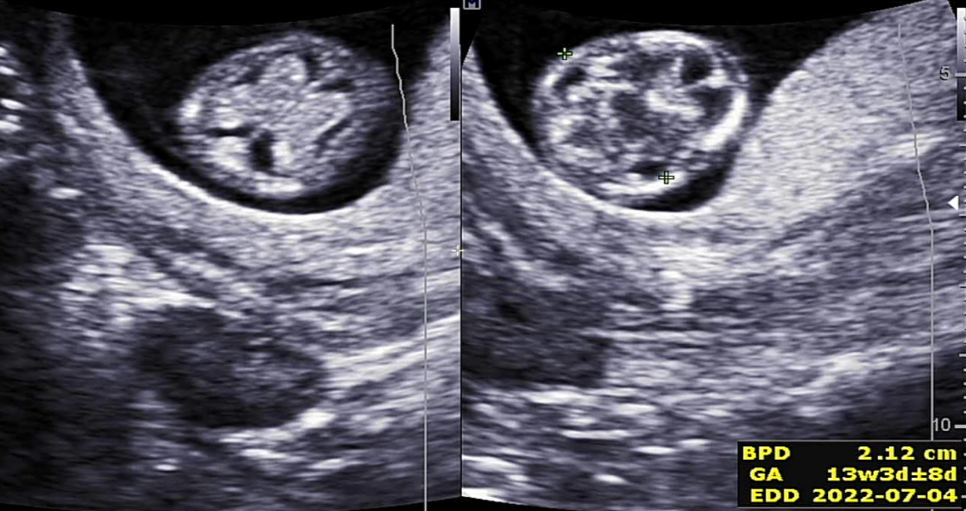

그다음에 본 뇌!# 임신기형아 검사를 통해 뇌 초음파는 처음 봤는데 뇌가 나비 모양이었죠? 다들 알고 계셨군요…굉장히 신기했던 뇌가 나비 모양으로 잘 성장했는지 머리 옆의 길이를 쟀습니다. 가로 길이는 2cm 정도 나왔습니다. ~